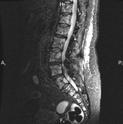

Ryc. 4.5. MRI – rozlany naciek szpiku.

Obecnie stanowi złoty standard w obrazowaniu zajęcia szpiku kostnego i zmian pozakostnych. Podanie środka kontrastowego nie jest potrzebne, ponieważ obrazy MRI cechują się wysoką rozdzielczością, dzięki czemu ocena nacieku szpiku tą techniką jest możliwa jeszcze przed pojawieniem się zmian litycznych kośćca w konwencjonalnym badaniu radiologicznym czy tomografii komputerowej. Zmiany ogniskowe uwi-

docznione w MRI korelują ze standardowymi czynnikami prognostycznymi (w tym cytogenetycznymi) i wynikami leczenia. Obecność więcej niż jednej zmiany ogniskowej w MRI jest najsilniejszym niekorzystnym czynnikiem prognostycznym w MRI, stanowiąc biomarker nowotworu uwzględniony w kryteriach rozpoznania szpiczaka. Obrazowanie kręgosłupa w MRI zapewnia ocenę potencjalnych powikłań mechanicznych złamań kręgów czy rozległych zmian w kanale kręgowym zagrażających kompresji rdzenia kręgowego i korzeni nerwów rdzeniowych.

Kwestię limitującą powszechne wykorzystanie rezonansu magnetycznego całego ciała we wstępnej diagnostyce szpiczaka plazmocytowego stanowi długi czas akwizycji danych, przekładający się także na większe ryzyko powstawania artefaktów ruchowych.